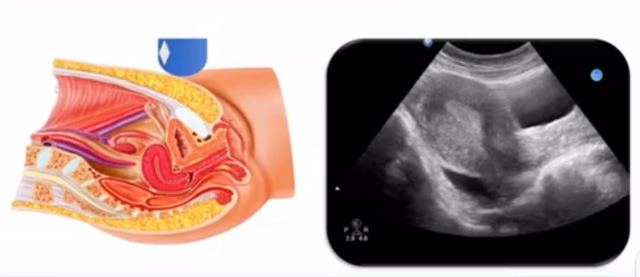

女性生殖系统包括内、外生殖器官及其相关组织以及邻近器官,其中内生殖器是我们超声检查的主要对象。那么内生殖器包括阴道、子宫还有输卵管及卵巢。输卵管及卵巢称为子宫附件。子宫是倒置梨形,但是它是空腔厚壁肌性器官。它的正常值在育龄妇女。超声探头放在贴近腹壁盆腔上面位置,来看这个子宫在超声上面的表现。从轮廓上来讲,和示意图是一样的。这就是在超声上面显示的一个子宫的图片。子宫在不同的时期与子宫颈的比例。成年妇女指的是育龄妇女为2:1子宫体是比较大的,婴儿期为1:2说明宫颈比较大,绝经期1:1。所以我们在看到子宫图时候可以根据宫体宫颈比例大致可以推测属于哪个时期的妇女。另外还可以根据比例大小来推断是一个正常子宫还是异常子宫。

子宫从外到内,浆膜层、肌层、粘膜层。宫体部宫颈为梭形结构。宫腔为上宽下窄的三角形,连接为峡部。子宫有什么功能呢?月经血产生跟排出通道,精子运行通道受精作用。囊胚着床及胎儿发育、生长的场所。分娩时产生宫缩使胎儿、胎盘娩出。未孕的子宫是很小的,已孕子宫就非常大,平均胎儿都有6斤重。所以这个后壁就体现出来。输卵管由子宫角部向外延伸,为一对细长而弯曲的管道,呈管状中空结构,大概长度是8-14厘米,粗1-4毫米,它的下方为卵巢和阔韧带。间质部是厚一点的,峡部是比较窄的地方,壶腹部,漏斗部。正常情况下,输卵管在普通超声DR难以显示。